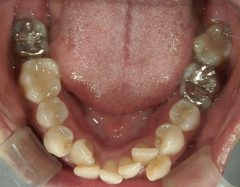

矯正歯科 治療前矯正歯科 治療前

矯正歯科 治療前 上下左右4番 計4本を抜歯して叢生を改善しました。

矯正_灰色.pngno.31_1962_治療前_上.JPG矯正_灰色.png

矯正_灰色.pngno.31_1962_治療前_下.JPG矯正_灰色.png